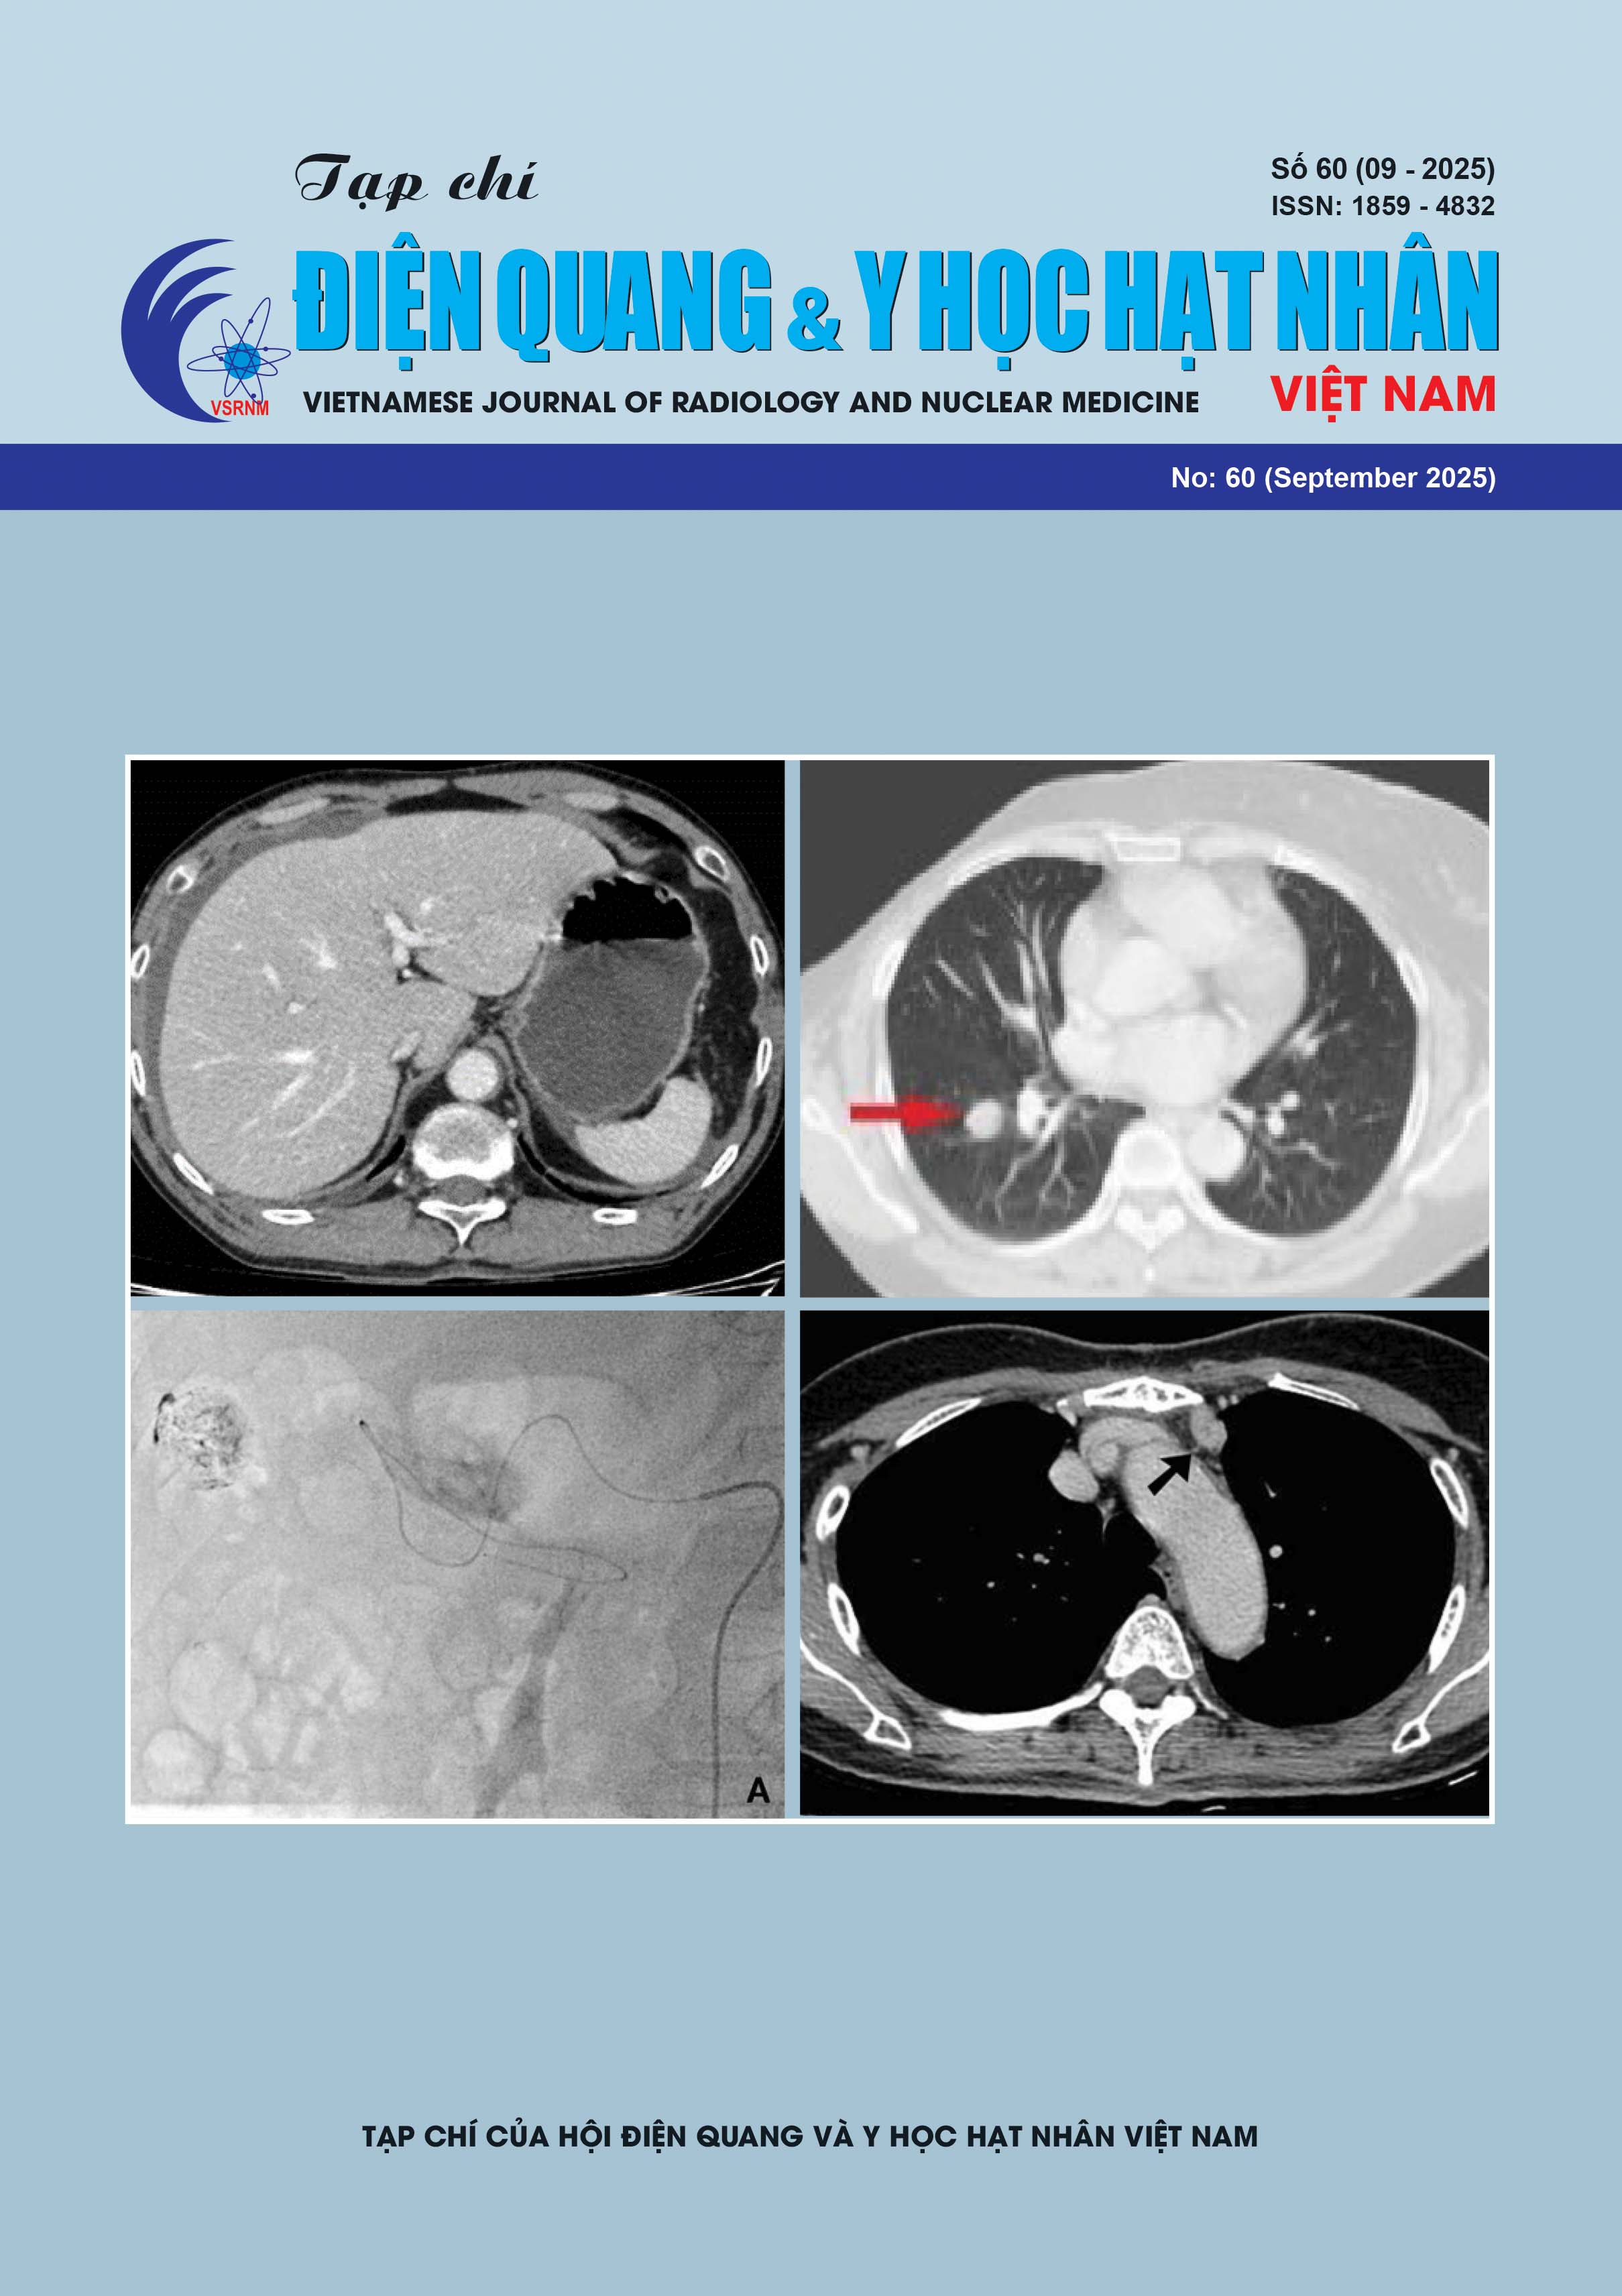

Comparison of Computed Tomography Characteristics between Pulmonary Adenocarcinoma and Squamous Cell Carcinoma at Bach Mai Hospital

Prognostic Value of Tumor-to-Mediastinal Lymph Node SUVmax Ratio on PET/CT in Predicting Nodal Metastasis in Patients with Non-Small Cell Lung Cancer

Relationship between EGFR mutation and computed tomography features in patients with non-small cell lung cancer

Role of Dual-Energy CT in Evaluating Urinary Stones

Magnetic Resonance Imaging Features of a Case Series of Intraductal Papillary Neoplasms of the Bile Duct

Primary Klebsiella Pneumoniae Liver Abscess from the Viewpoint of Radiologist: 3 Case Reports and Literature Review